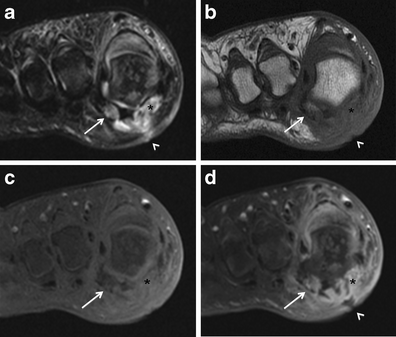

Osteomyelitis in the hallucal sesamoids. Short-axis coronal T2-weighted (a) and T1-weighted (b) MRIs in the same patient as Fig. 12 show complete destruction of the medial hallucal sesamoid (asterisk) and intense bone marrow oedema with T1 hypointensity in the lateral hallucal sesamoid (arrow). Severe soft tissue oedema is seen in the surrounding soft tissues, extending to a plantar cutaneous defect (arrowheads). Pre-contrast (c) and post-contrast (d) fat-saturated T1-weighted MRIs reveal intense enhancement of the medial and lateral sesamoids (asterisks, arrows) and the adjacent soft tissues. Note the ulceration in the plantar soft tissues (arrowhead, a, b, d)